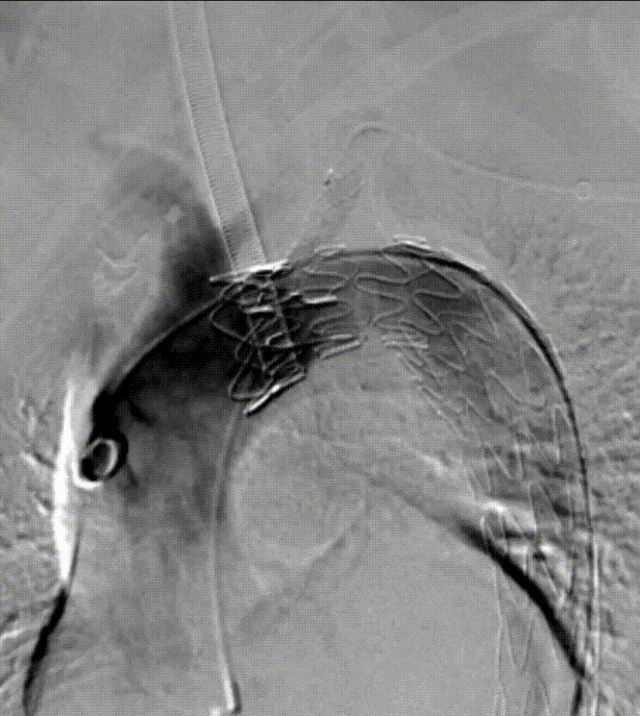

★预开窗技术(PMEG)

近10年来,本中心从单开窗到三开窗不断探索,积累了一些研究材料,发表了几篇文章。总体来看,单开窗本中心42个月随访显示:左锁骨下动脉通畅率100%,三年生存率达96%。与全国多中心合作研究的513例多分支预开窗重建病例显示,随访两年多,技术成功率达98.6%,并发症发生率为9.2%,死亡率为2.4%,满足当前治疗需求。需要注意的是,该手术受限于术前规划精度。

PMEG--预开窗技术

PMEG重建LSA的近中期研究结果

PMEG重建多分支的近中期研究结果